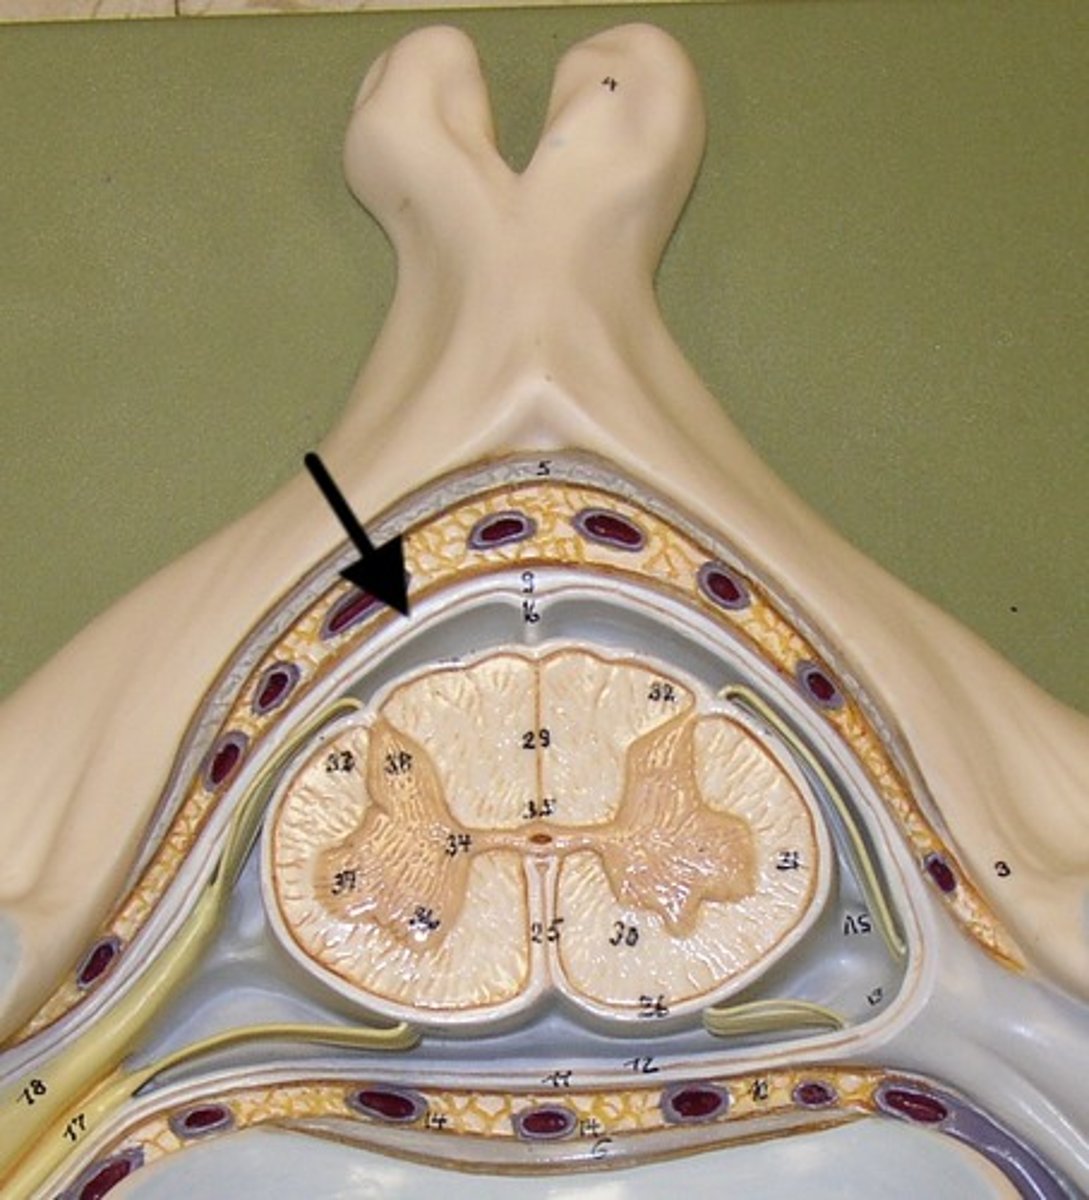

Spinal cord Anatomy (cross-sectional)

1)Internal butterfly shaped gray matter,

2)Exterior white matter,

3)Central canal filled with cerebrospinal fluid (CSF),

4)Cushioned & protected by meninges,

5)Pia mater,

6)Spinal nerves leave at the level of each vertenrae

Horns of Spinal Cord Anatomy

Dorsal Horns,

Ventral Horns,

Lateral Horns

Dorsal Horns

Lateral Horns

Ventral Horns

Interneurons

exterior white matter of the spinal cord

Ascending (sensory) and descending (motor) myelinated nerve tracts,

Posterior, anterior, lateral columns or funiculi

Posterior Columns

Anterior Columns

Lateral Columns/ funiculi

Central canal filled with what?

Central canal filled with cerebrospinal fluid (CSF)

Cushioned and protected by meninges

1) Cover the spinal cord

2) Dura mater, Arachnoid & Pia mater

dura mater of spinal cord

1) Separated from the periosteum by the epidermal space (fat, blood vessels)

2) Subdural space between dura and arachnoid mater

Dura Mater